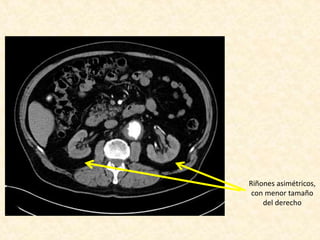

• Riñones levementes asimétricos por menor tamaño del

derecho

Riñones asimétricos,

con menor tamaño

del derecho

Informe • Leve dilataciónde arco aórtico • La aorta descendente se presenta elongada, tortuosa y presenta un gran aneurisma que compromete gran parte de su extensión, el cual se inicia aproximadamente 6 cm del origen de la subclavia izquierda, se extiende por aproximadamente 15 cm, y alcanza un diámetro máximo de 10 cm, con trombosis aproximadamente del 60% de la luz. • La aorta abdominal es tortuosa, con ateroma severo de predominio de placas no calcificadas, sin aneurismas. • Estenosis crítica de la arteria renal derecha • Riñones levementes asimétricos por menor tamaño del derecho